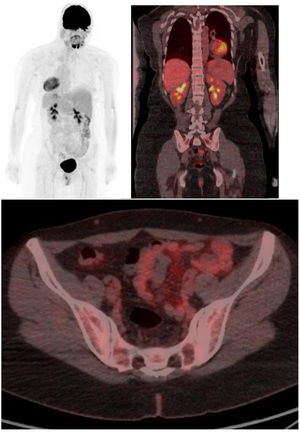

Tomografía por emisión de positrones (PET/TC) con fluorodesoxiglucosa F-18 (FDG) de cuerpo entero con reconstrucción con proyección de máxima intensidad (MIP), coronal y axial fusionados

Se aprecian focos de captación fisiológica como son cerebro, corazón, ambos riñones y vejiga y ausencia de captaciones ósea patológicas, lo que lo diferencia de metástasis u otras enfermedades óseas sugerentes de malignidad.